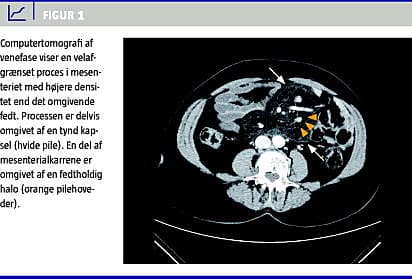

Patientens abdominale CT blev vurderet på en multidisciplinær tumorkonference. Her fandt man en 9 × 14 × 20 cm stor mesenterial tumor, der omkransede de centrale mesenterielle kar. De mesenterielle kar af normal kaliber var uden tegn på indvækst, og adskillige kar var omgivet af fedtholdig halo (Figur 1 ). Tumoren havde relation til både tynd- og tyktarm uden tegn på indvækst. Der var ingen forstørrede lymfeknuder intraabdominalt. Lever, milt, nyrer, binyrer og pancreas var normalt udseende. Det blev vurderet, at fundet var foreneligt med MP.